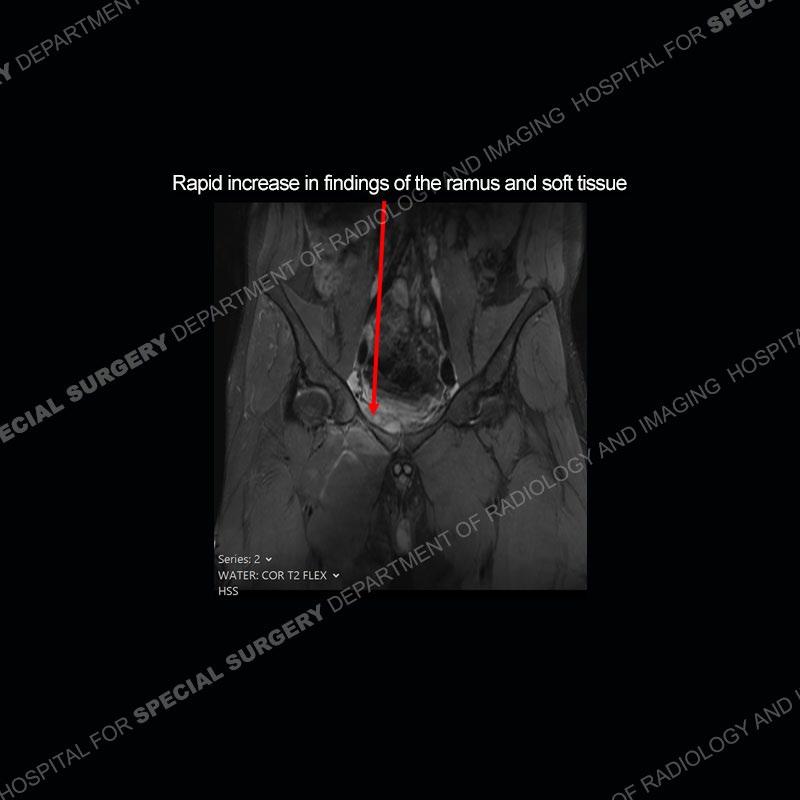

Subsequent MRI in a very short time interval shows markedly increased abnormality of the ramus and increased edema and “mass” of the soft tissue. Post contrast imaging shows multiple, rim enhancing collections of the soft tissue and similar albeit less conspicuous enhancing collection of the ramus.

The repeat MRI, with the marked degree of increased abnormality of the bone and soft tissue shifted the diagnosis to a high degree towards infection. Even the most aggressive of neoplasms would not have that the degree of change in a 3-day time span. The CT study was shown before the repeat MRI but actually occurred just after the repeat MRI. It helped confirm the destructive process of the ramus and particularly the abnormal architecture along the inferior margin. The patient went on to have a CT guided aspiration of one of the soft tissue collections with 4cc of purulent fluid obtained. A surgical irrigation and debridement of the bone and soft tissue was performed. A PICC line was placed and the patient is currently undergoing IV antibiotic treatment with a possible repeat irrigation and debridement.